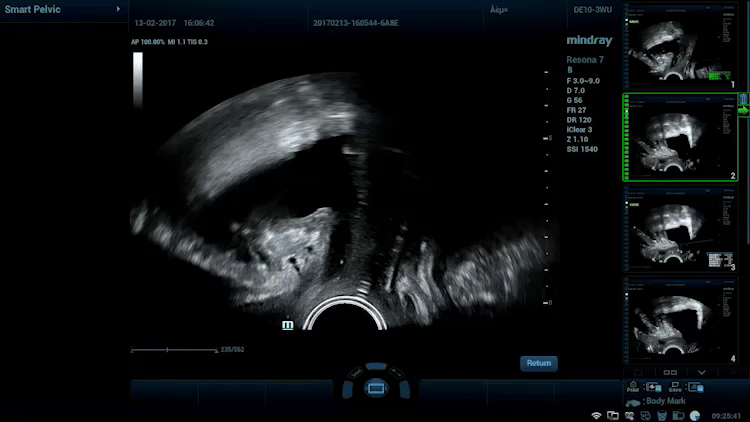

Smart Pelvic

Nhận thấy tầm quan trọng ngày càng tăng của siêu âm trong chẩn đoán các rối loạn sàn chậu, Smart Pelvic mang đến một giải pháp mới giúp đơn giản hóa đáng kể quy trình thao tác và rút ngắn thời gian thăm khám cho một đánh giá chuẩn hóa về sàn chậu. Với thao tác cực kỳ đơn giản cho người dùng, hệ thống sẽ tạo ra một hệ tọa độ chuẩn và tự động cung cấp tất cả các phép đo liên quan chỉ trong vài giây.